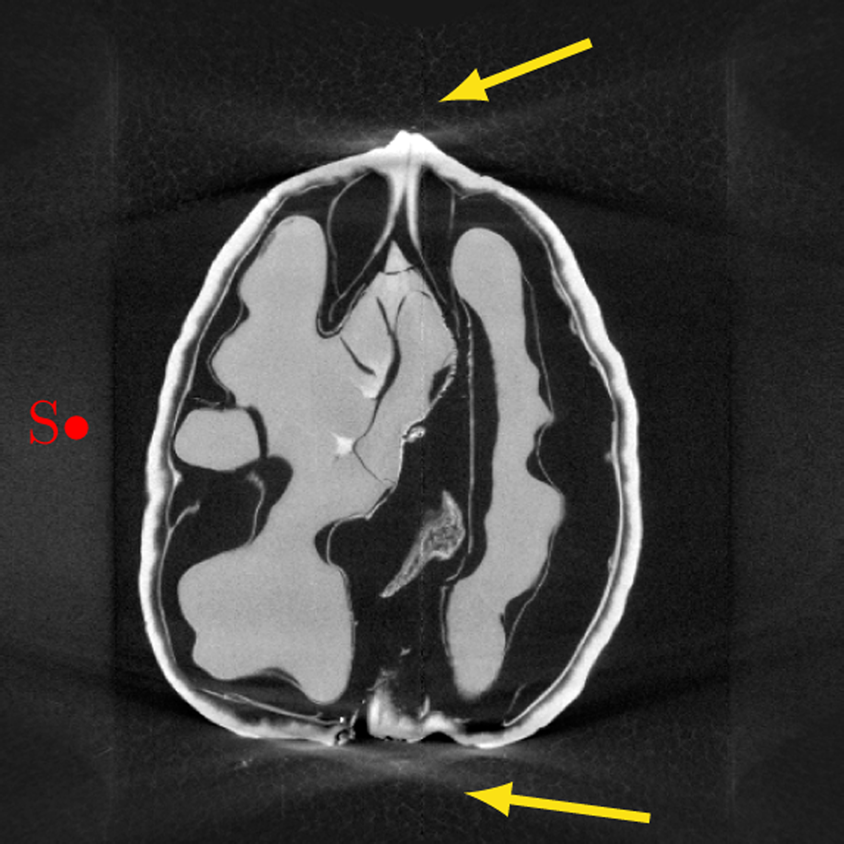

Calculation Of Brain Atrophy Using Computed Tomography And A

3d Processing And Analysis With Imagej